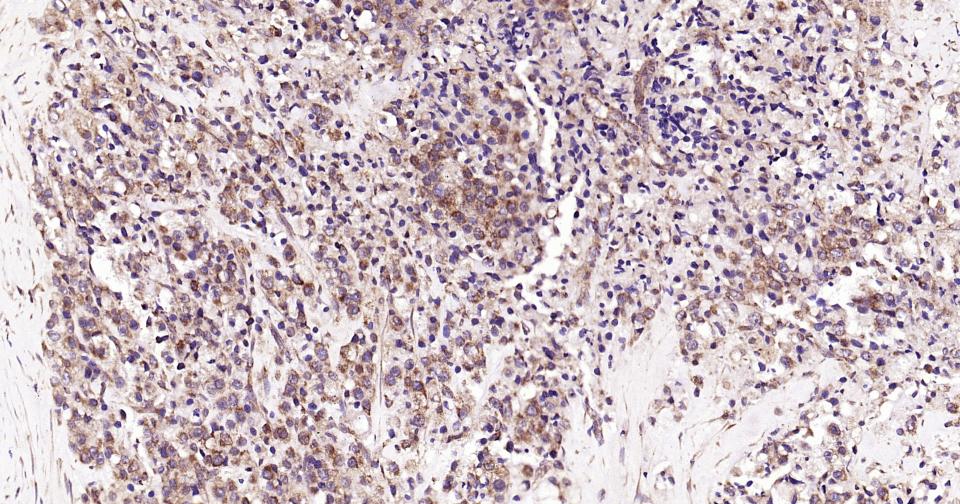

Paraformaldehyde-fixed, paraffin embedded Human Prostate Tumor; Antigen retrieval by boiling in sodium citrate buffer (pH6.0) for 15 min; Antibody incubation with SCF Monoclonal Antibody, Unconjugated(bsm-61250R) at 1:200 overnight at 4°C, followed by conjugation to the SP Kit (Rabbit, SP-0023) and DAB (C-0010) staining.